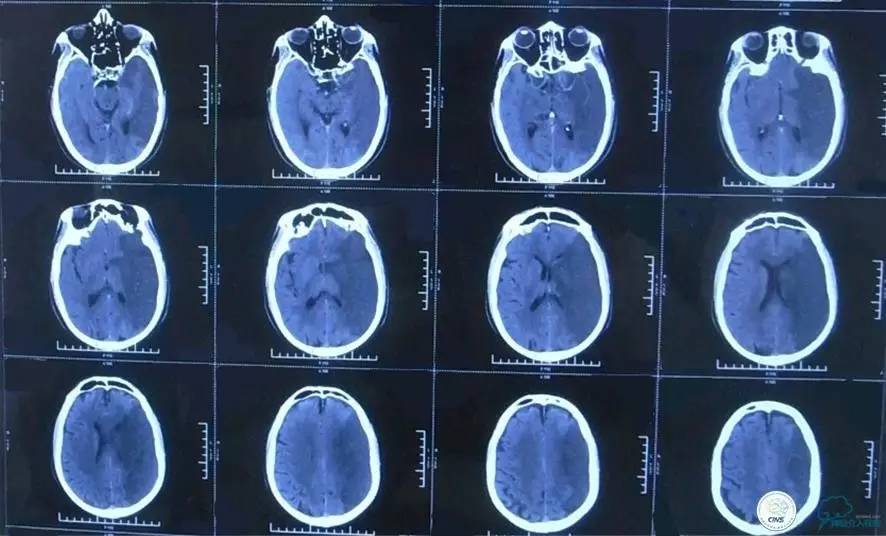

▼2015-06-05颅脑CT

患者时间窗内,发病3h开始静脉溶栓。rt-PA9mg/kg,70mg,7mgIV;63mg微量泵注入1h。期间患者症状改善不明显。观察时间后,仍无改善。遂介入交接治疗。

2015-06-05脑血管造影:左侧颈内动脉闭塞。

评估患者侧支循环,考虑患者发病时间超过6个多小时,未行血管内治疗。